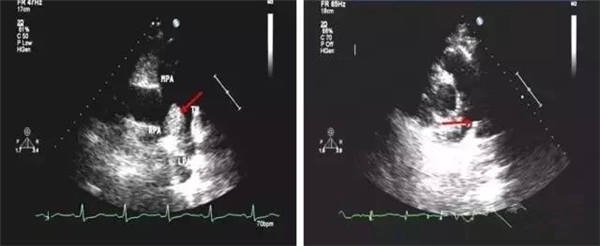

血栓

血栓是血栓性肺栓塞最典型的特征,位于右房或右室中的血栓可形态各异,而位于肺动脉内时则常表现为大块血栓,从主干延续至一侧或双侧肺动脉分支。右肺动脉主干血栓易于显示,左肺动脉因显示较短,血栓不易显示。此外,需注意将血栓与右心系统肿瘤相鉴别。

右心血栓 肺动脉血栓

正常的主肺动脉直径(MPA)<30 mm,左肺动脉&右肺动脉( LPA&RPA)<20 mm;而血栓栓塞性肺动脉高压(EPH)患者的MPA>30 mm,LPA&RPA>20 mm;慢性血栓栓塞性肺动脉高压(CTEPH)患者的MPA扩张则更加明显。

正常肺动脉